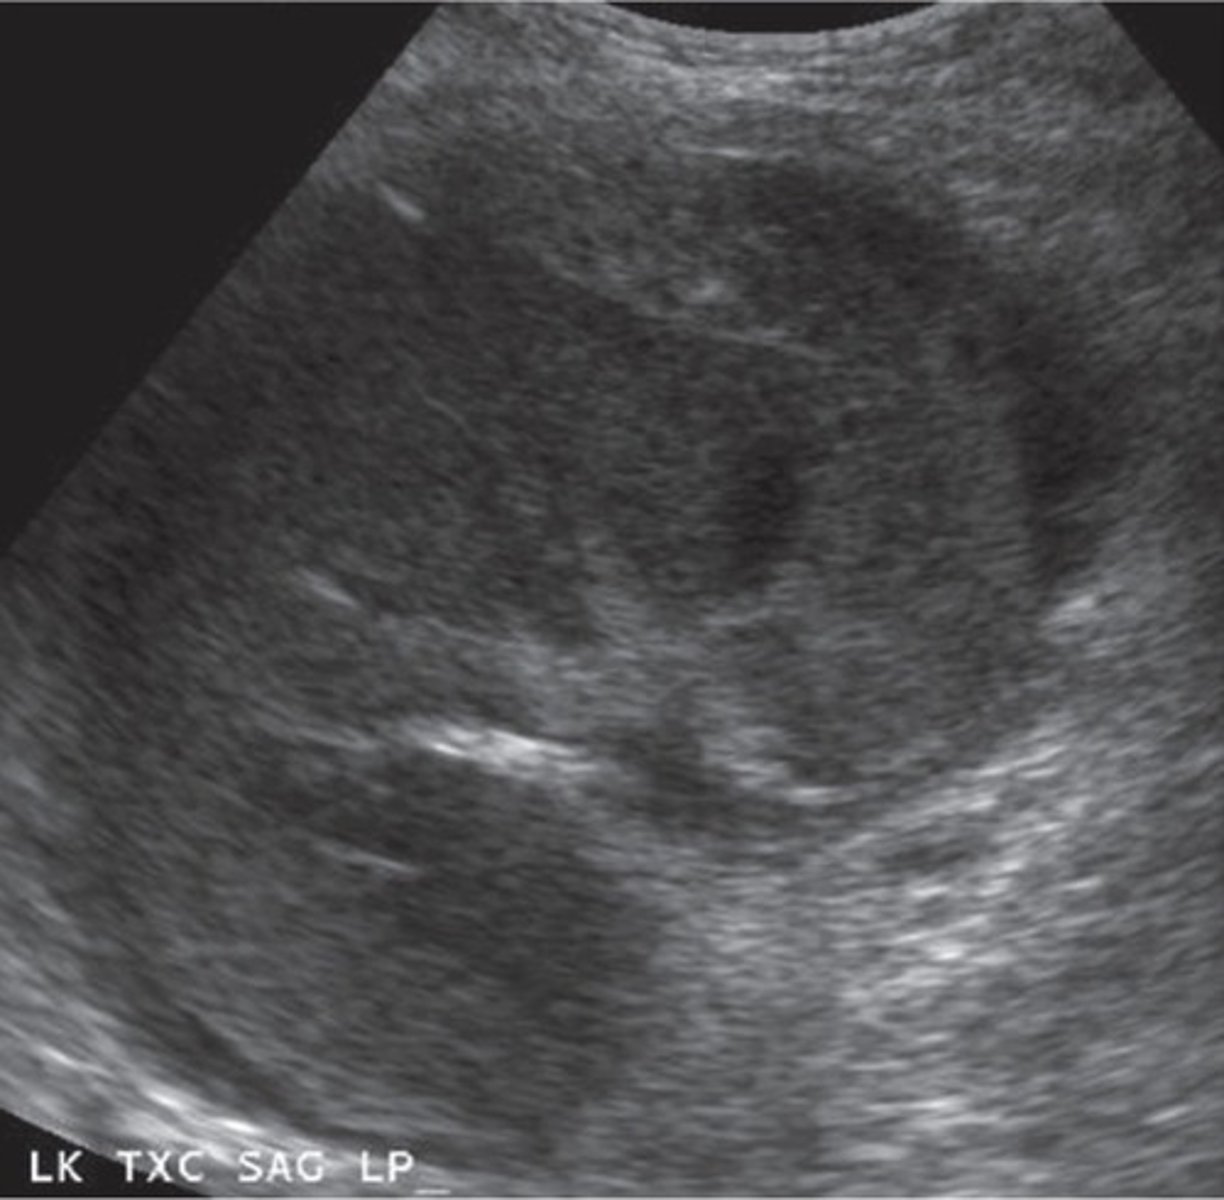

Hydronephrosis Post-Transplant

Due to ureteral narrowing from surgery

Compresses ureter and parenchyma

Increased RI